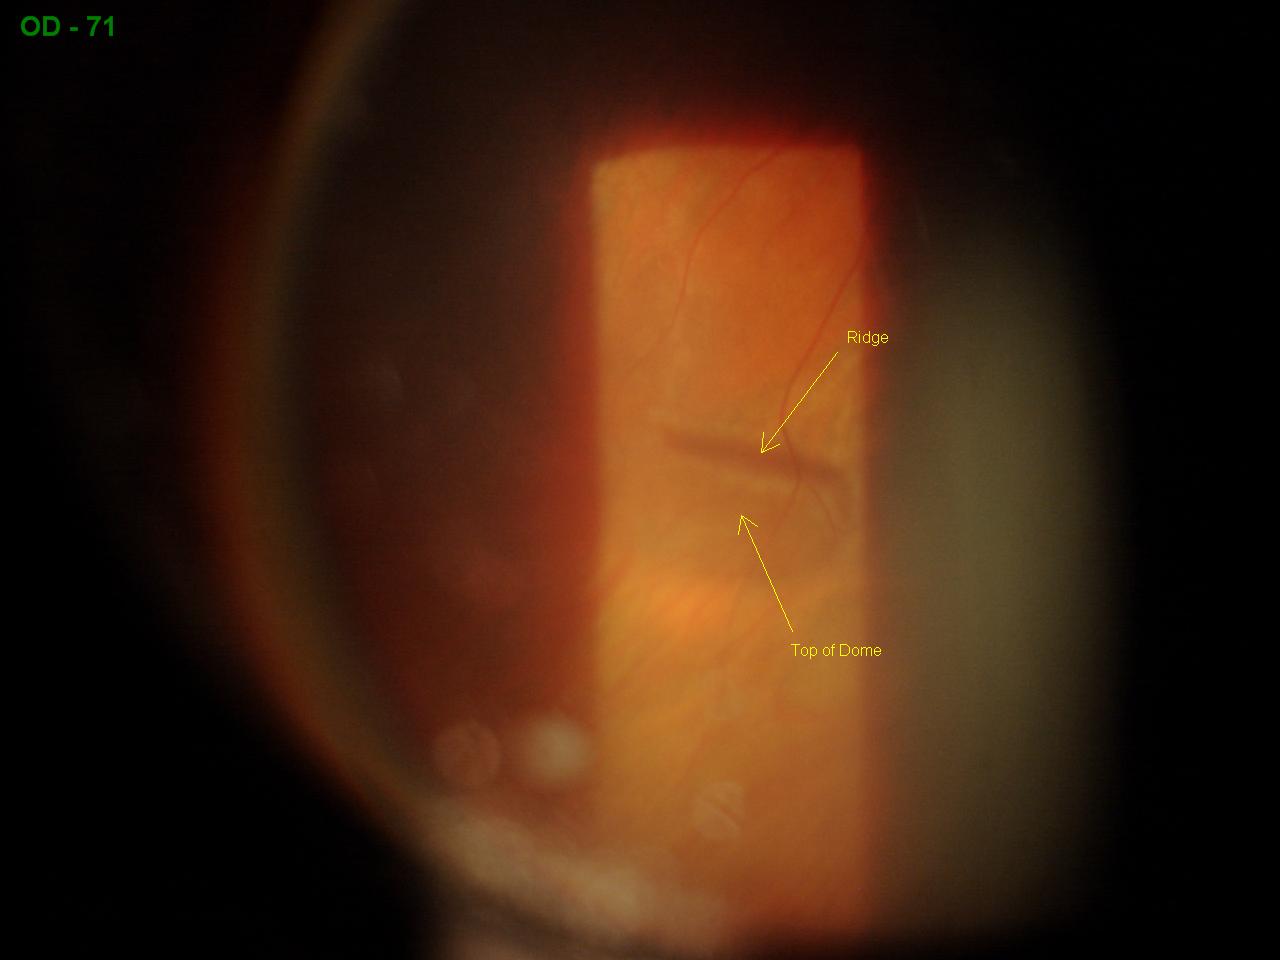

From sonorandeserteye.blogspot.com

Sonoran Desert Eye Center UNUSUAL RETINOSCHISIS What Does Retinoschisis Look Like It can affect young and old, and may lead to vision loss or complications. retinoschisis is an eye condition that causes the retina to split into two layers. Learn about the types, diagnosis, and treatment of retinoschisis. Retinoschisis is a rare eye condition that splits the retina into two layers, while retinal detachment is a medical emergency that separates. What Does Retinoschisis Look Like.